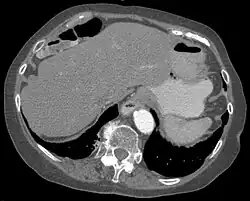

Chilaiditi-Syndrom in der Computertomographie axial

Das Syndrom ist eher selten (unter 1 %) und wird meist als Zufallsbefund auf Röntgenaufnahmen der Lunge, im Computertomogramm des Oberbauches oder im abdominellen Ultraschall erkannt. Bei Eingriffen an der Leber, insbesondere bei Leberpunktionen, ist die Kenntnis dieser anatomischen Variante von großer Wichtigkeit.

Es sind Anteile des Dickdarms – vor allem seine rechte obere Biegung (die Flexur) – oder seltener des Dünndarms zwischen den rechten Leberlappen und das rechte Zwerchfell verlagert. Das Syndrom kann mit Fehlbildungen der Leber, des Zwerchfells oder Dickdarmes einhergehen.